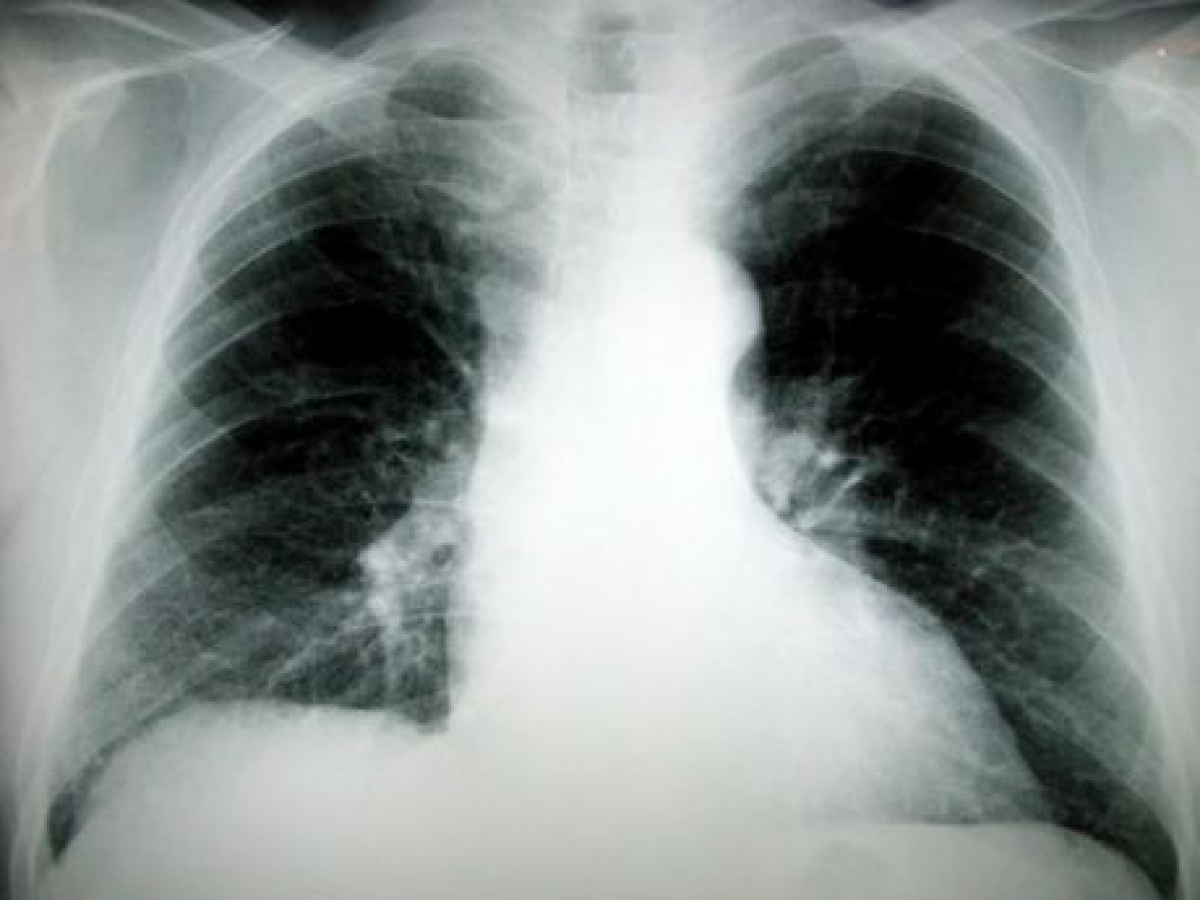

Η πρώτη δοκιμή έγινε σε έξι ποντίκια, στους πνεύμονες των οποίων είχε μεταμοσχευθεί ένας ιδιαίτερα επιθετικός καρκίνος των ανθρώπινων πνευμόνων. Όταν πλέον οι όγκοι είχαν αναπτυχθεί σε μέγεθος 150 κυβικών χιλιοστών (περίπου όσο μια σταφίδα), οι επιστήμονες άρχισαν να δίνουν ενδοφλέβια το νέο φάρμακο δύο φορές την εβδομάδα επί τρεις εβδομάδες.

Οι όγκοι συρρικνώθηκαν πολύ γρήγορα και συνέχισαν τη συρρίκνωσή τους ακόμη και μετά τη διακοπή της φαρμακοθεραπείας. Σε πέντε από τα έξι ποντίκια οι καρκινικοί όγκοι εξαφανίστηκαν τελείως σε 25 έως 29 ημέρες από την έναρξη της θεραπείας - χωρίς ορατές παρενέργειες λόγω τοξικότητας.

Ανάλογη αποτελεσματικότητα υπήρξε στη δεύτερη δοκιμή, που αφορούσε τη χορήγηση του ίδιου φαρμάκου από το στόμα κάθε μέρα επί δύο εβδομάδες. Και στα έξι ποντίκια υπήρξε πλήρης εξαφάνιση των όγκων στους πνεύμονές τους. Η μόνη παρενέργεια ήταν η μείωση του αριθμού των λευκοκυττάρων στο αίμα των πειραματόζωων μετά τη λήξη της θεραπείας, αλλά το πρόβλημα αποκαταστάθηκε μετά από δύο εβδομάδες.